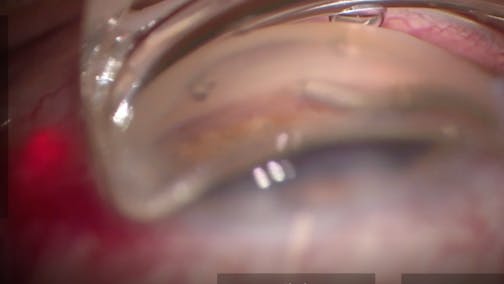

This video describes combining various MIGS procedures with complementary mechanisms of action. This patient was on four medications with IOP in the upper 30s and moderate progressing OAG. I didn't want to wait for surgery even with concerns over COVID-19. I was tempted to perform a trabeculectomy, but I wanted to decrease the potential for adverse events which would cause the patient to have to return to the office more often. I therefore chose 360-degree viscodilation, 180-degree trabeculotomy, and Hydrus implantation to maximize conventional outflow. I could always consider a subconjunctival surgery if needed in the future. Postop day 1 IOP was 14 mmHg and with 20/30 visual acuity.